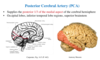

What are the names of these holes and which cranial nerves come out of each.

What do each of these do also?